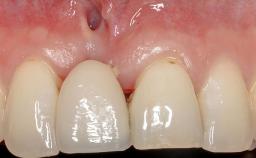

Soft-Tissue Volume Augmentation Using a Connective-Tissue Graft Harvested from the Maxillary Tuberosity

In 1983, a 51-year-old non-smoking patient was referred for the treatment of moderate chronic periodontitis. At the initial examination, 47% of sites exhibited probing depths of 4 to 6 mm. Periodontal therapy consisted of initial periodontal treatment including oral-hygiene instructions and supra- and subgingival debridement, followed by periodontal surgery to eliminate residual pockets.

Soft Tissue Grafting Simultaneous

Soft Tissue Anatomy Intact Defective